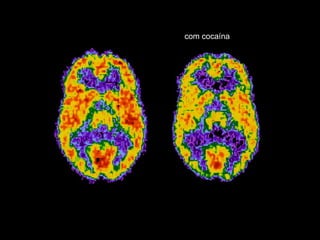

Que tipo de doença é a Dependência ? Dependência é uma doença cerebral crônica e recidivante As drogas mudam o cérebro, mudam a estrutura de como funciona.  Doença COMPLEXA

com cocaína

Importante O Cerebro pode ser reparado – Leva tempo Dependência como qualquer outra doença, pode ser gerenciada, e a pessoa viver sem a droga